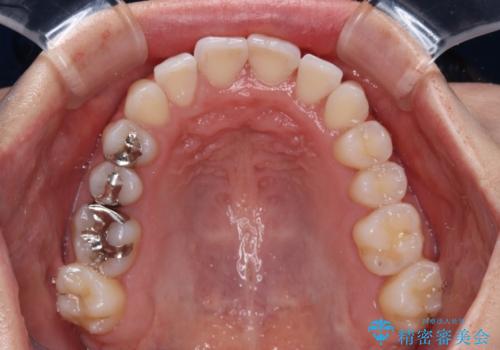

急速拡大装置により骨格はある程度改善されましたが、奥歯の咬み合わせ改善に非常に時間がかかってしまいました。

デコボコを改善させるだけでなく、しっかりとした咬合状態を獲得することができ、患者様には大変満足していただけました。